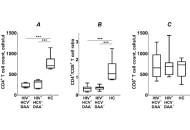

Assessment of CD4+ T cell recovery after direct-acting antiviral hepatitis C treatment in HIV/HCV coinfected immunological nonresponders to ARTOpen AccessOriginal ArticleAim: This study investigated the effects of successful hepatitis C virus (HCV) treatment with direct-acting antivirals (DAAs) on CD4+ T cell recovery in HIV/HCV coinfected immunological non-respo [...] Read more.Violetta Vlasova ... Konstantin ShmagelPublished: May 21, 2025 Explor Med. 2025;6:1001323

Assessment of CD4+ T cell recovery after direct-acting antiviral hepatitis C treatment in HIV/HCV coinfected immunological nonresponders to ARTOpen AccessOriginal ArticleAim: This study investigated the effects of successful hepatitis C virus (HCV) treatment with direct-acting antivirals (DAAs) on CD4+ T cell recovery in HIV/HCV coinfected immunological non-respo [...] Read more.Violetta Vlasova ... Konstantin ShmagelPublished: May 21, 2025 Explor Med. 2025;6:1001323